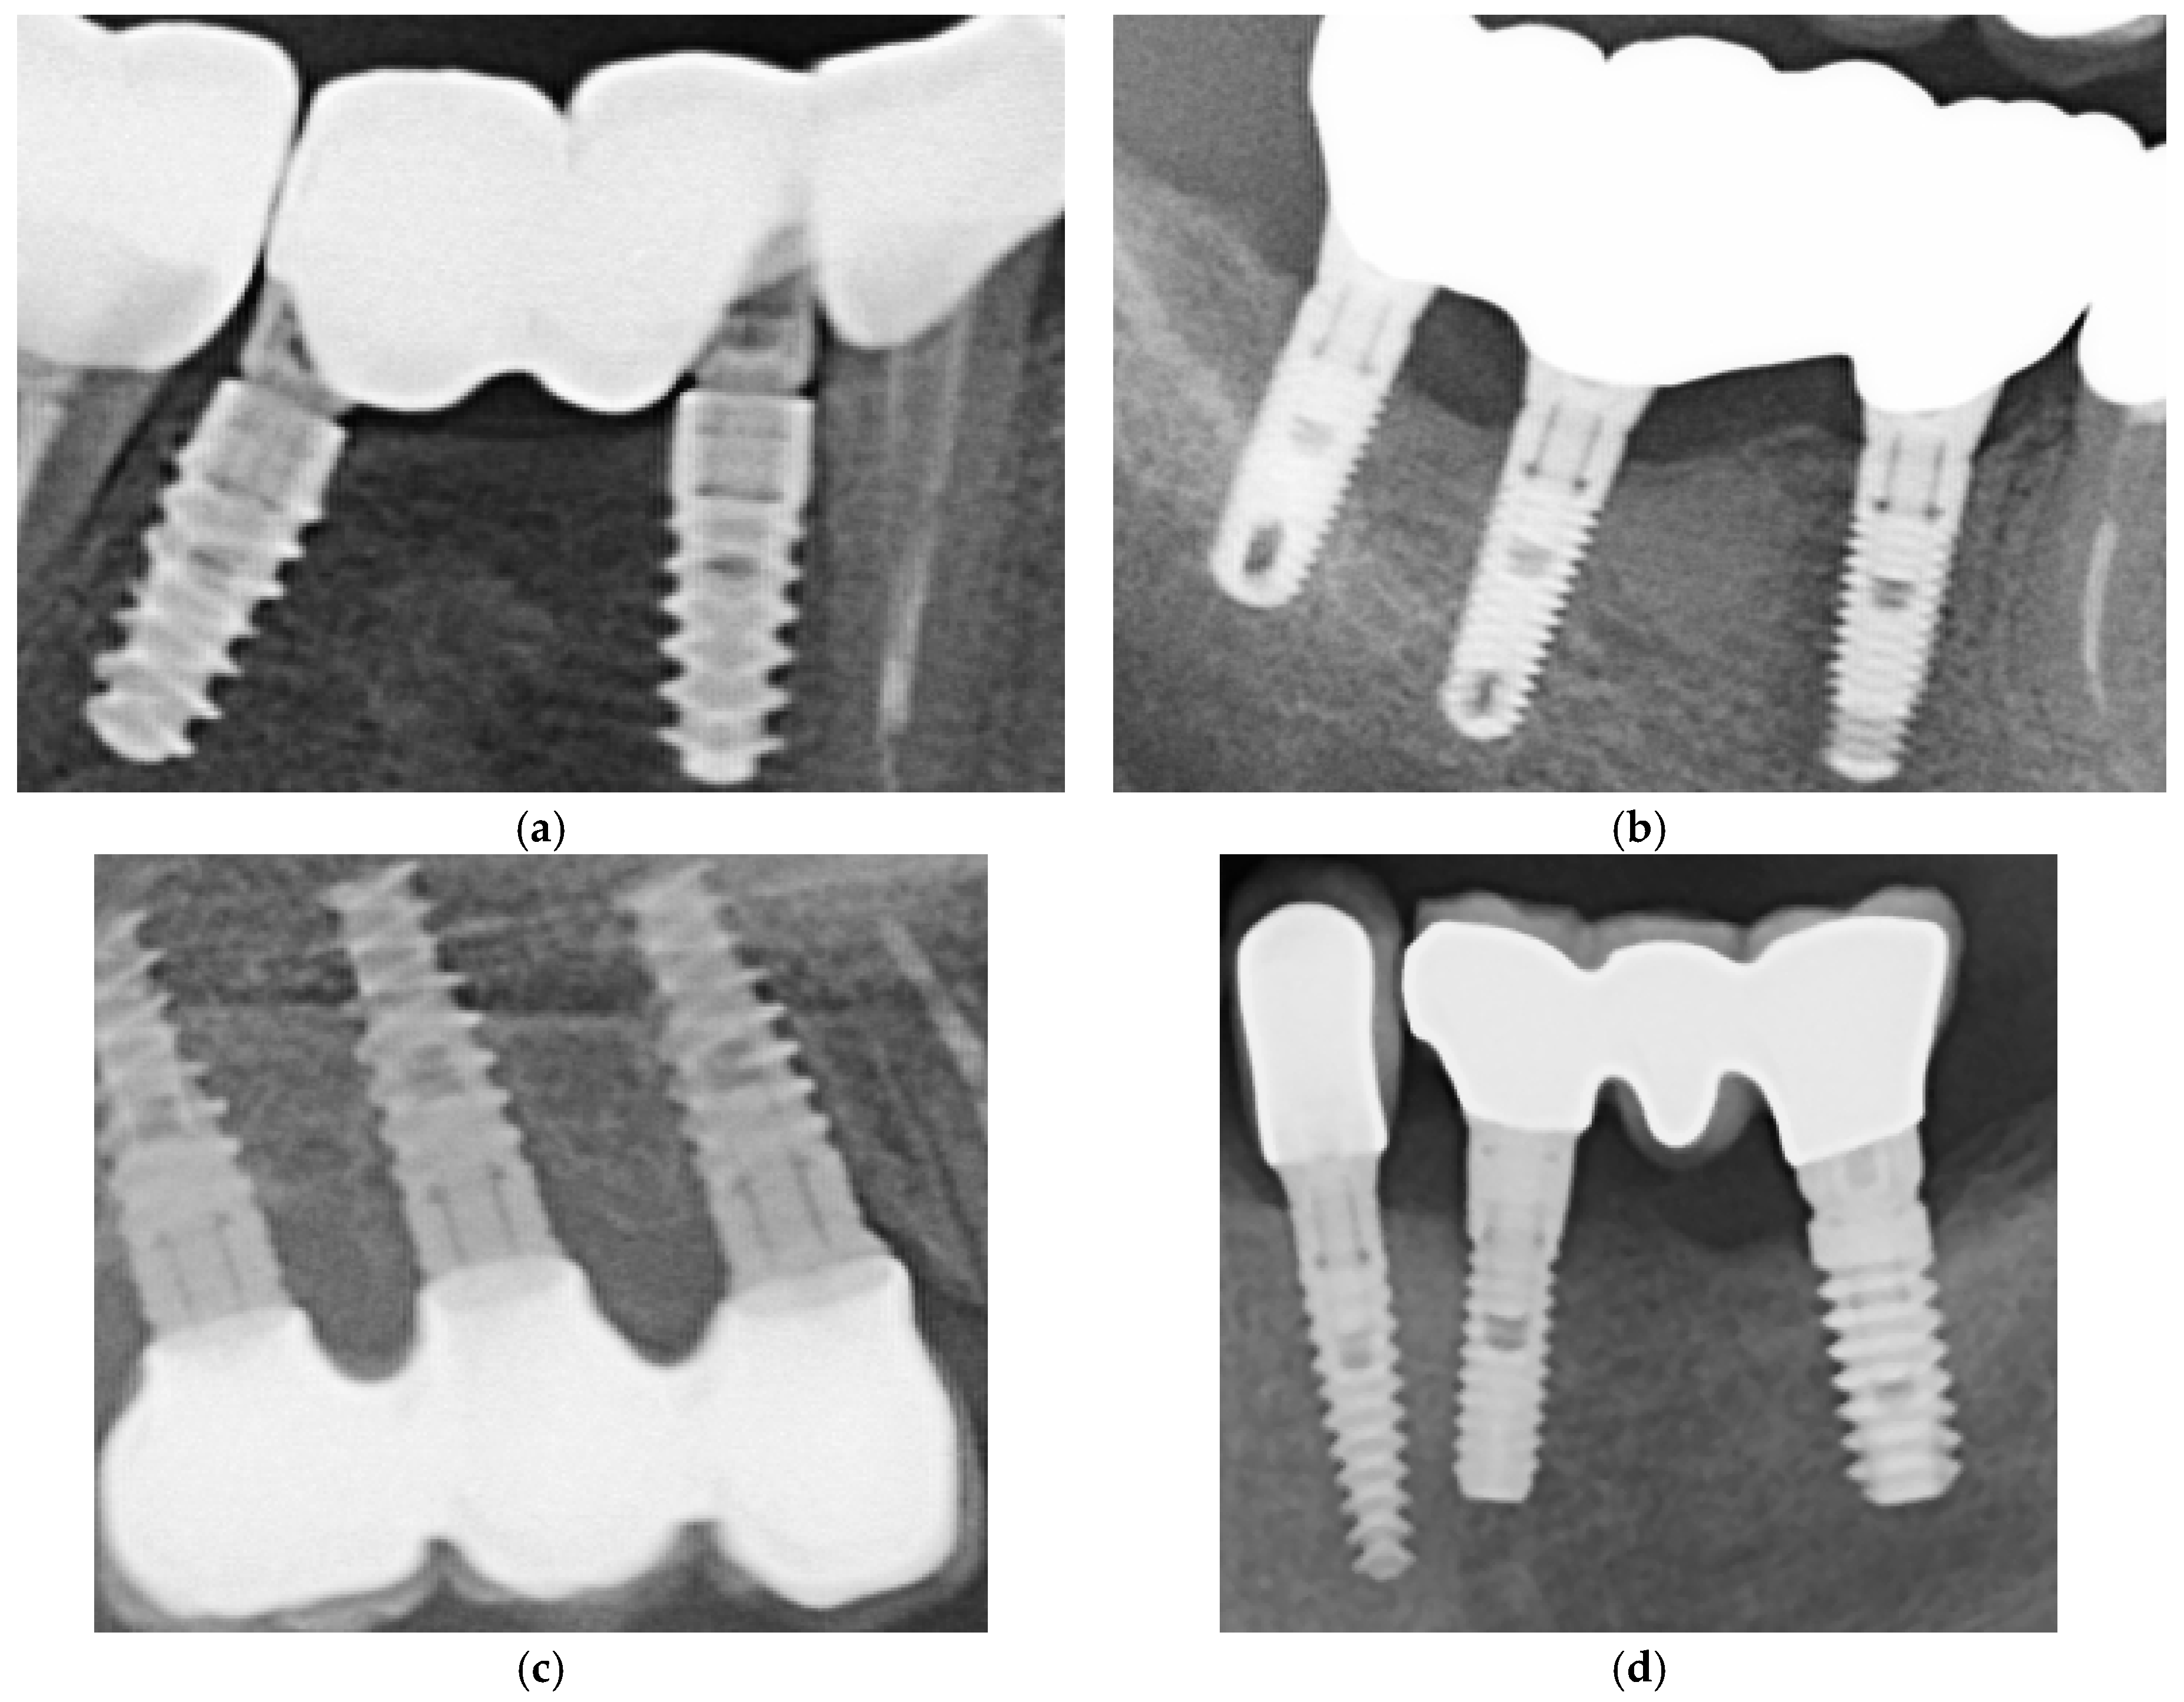

Restorations were ultrasonically cleaned in isopropyl alcohol or ethanol for five minutes, air-dried, and stored in a clean container prior to cementation. In Figure 3, photos of these two types of restorations are shown, from different angles, in order to see the characteristics of both surfaces.

Figure 3. Examples of zirconia (a) and metal–ceramic (b) restorations. The zirconia samples illustrate partial fixed prostheses, while the metal–ceramic examples include a full-arch prosthesis shown only for material demonstration purposes. Full-arch cases were not part of the study cohort.